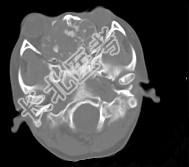

- 多项选择题男性,28岁, 因鼻塞、头痛1年余,鼻窦CT扫描如图所示, 请选择正确的描述与结论 ( )

A、双侧上颌窦、筛窦、鼻腔及蝶窦内见软组织肿块影

B、肿块内密度不均,有较多致密钙化影

C、窦壁及颅底骨质破坏